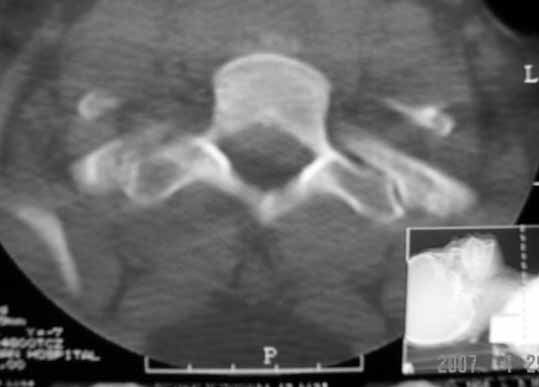

以下是引用zhangzhongshou在2007-4-29 22:53:00的发言:[br]1、c5半脱位,i度前滑脱。[br]2、c5椎板骨折。[br]3、第7幅图像显示右侧椎板骨折,哪一节颈椎,楼主自己知道。[br]4、c2、3附件融合畸形。[br]5、考虑环椎后桥,亦为正常变异。